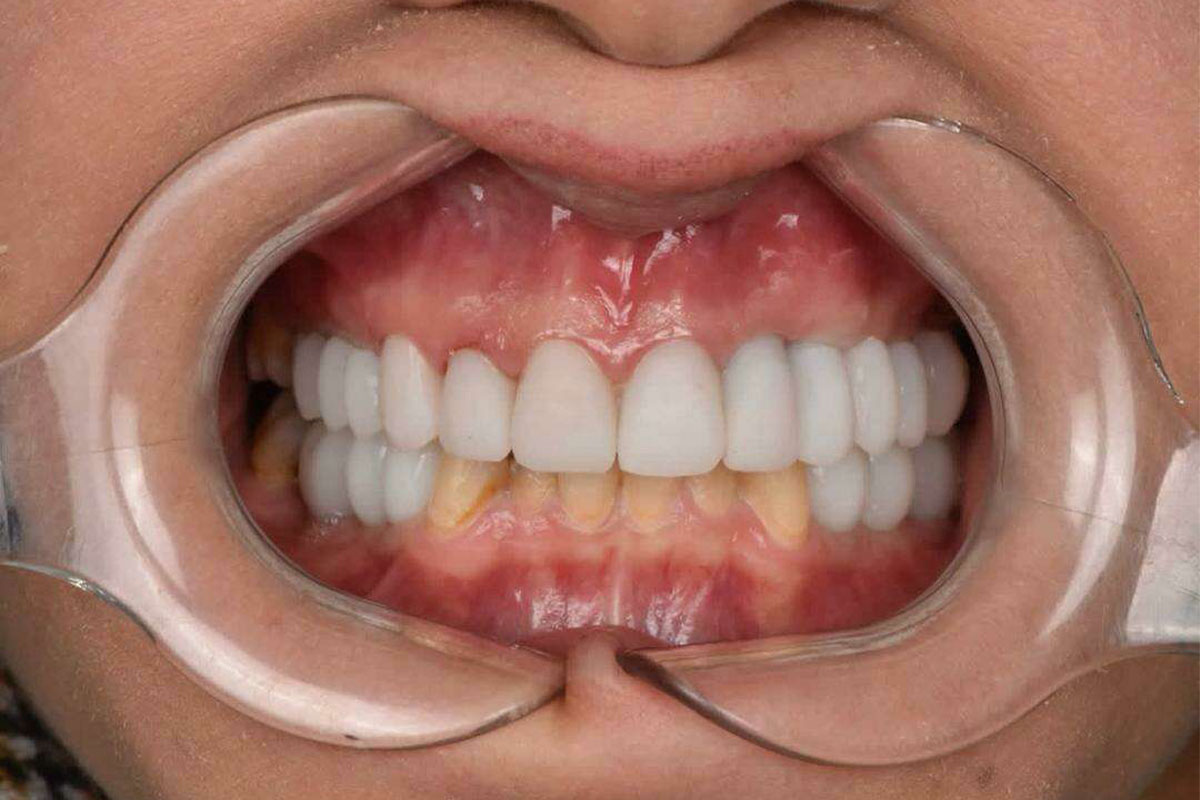

نمونه درمان های ایمپلنت

نماذج من علاجات الفیشور سيلانت